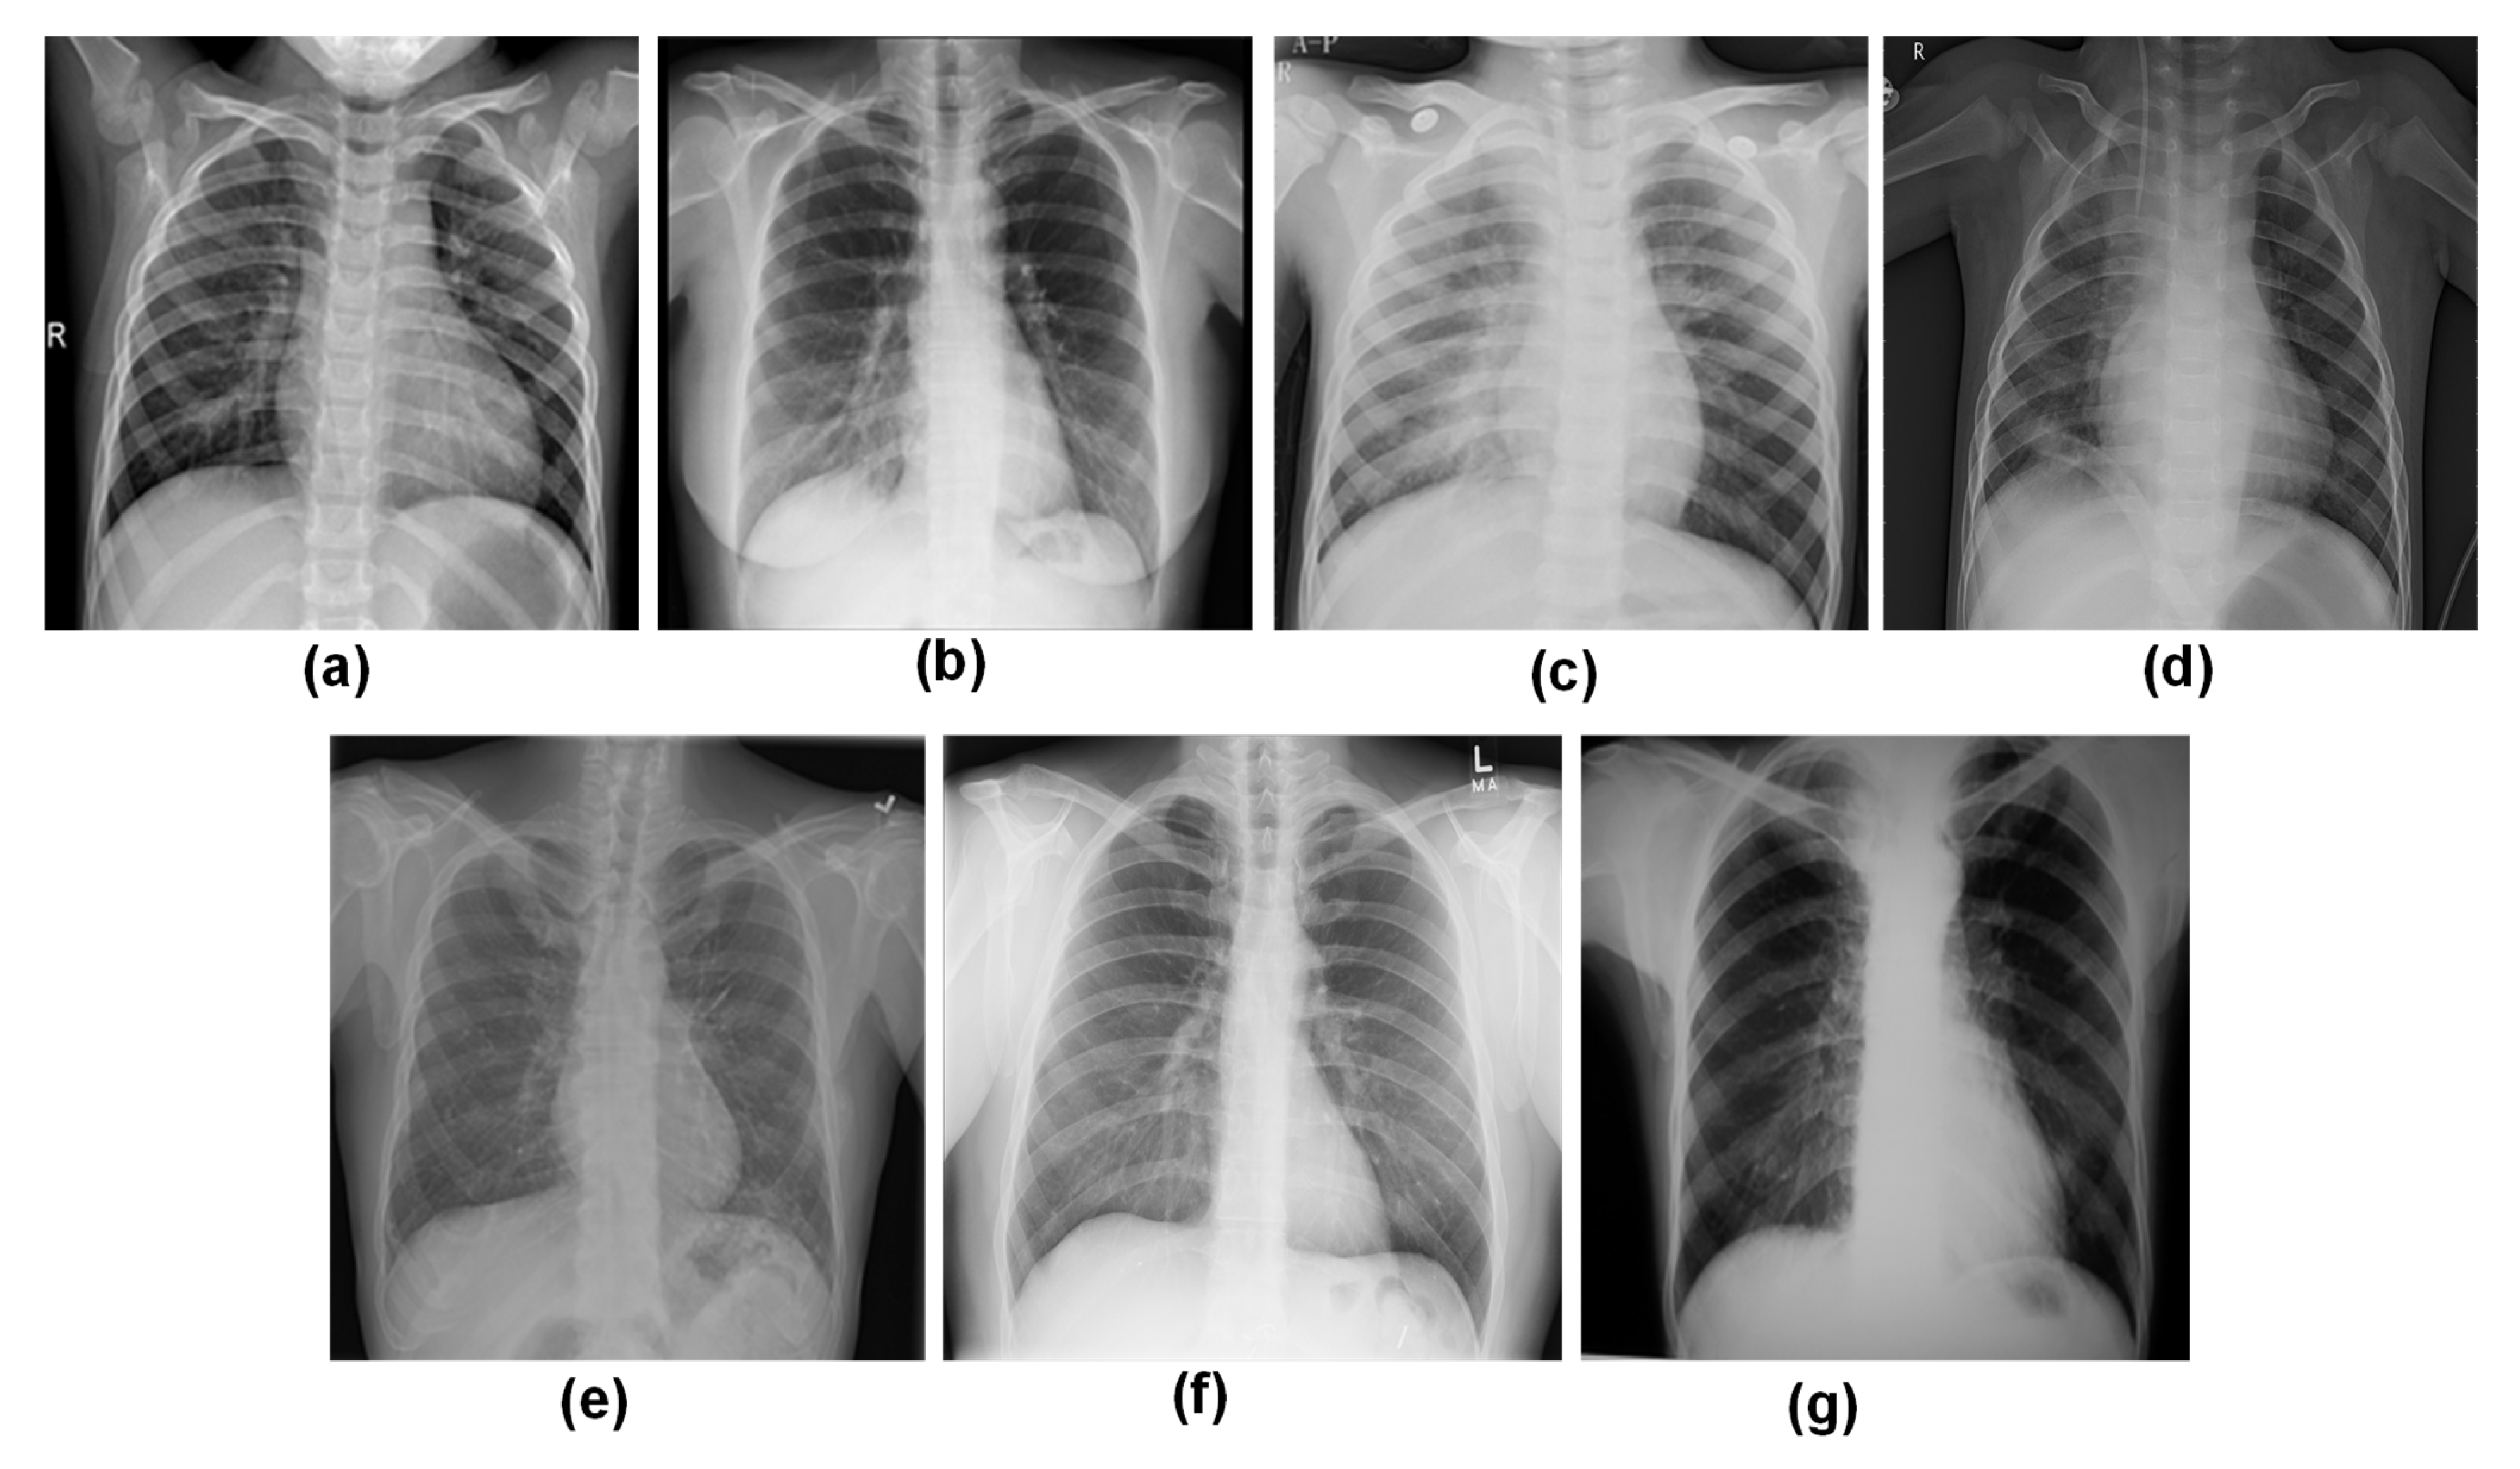

3.1. Data Collection

3.1.1. COVID-19 Radiography Database

3.1.2. Viral Pneumonia vs. Bacterial Pneumonia Database

3.1.3. CXR Database for Tuberculosis (TB) and Fibrosis

3.1.4. New Dataset Creation

| Dataset | Image Count | Characteristics | New Dataset Inclusion Criteria |

| COVID-19 Radiography Database [29]  | Normal: 3616 Lung Opacity: 3616 COVID-19: 3616 Viral Pneumonia: 1345  | The size of each image is 299 × 299 pixels and PNG format | Each of the four class images is employed in this study. |

| Pneumonia Virus vs. Pneumonia Bacteria Database [30,31] | Bacterial Pneumonia: 2530 Viral Pneumonia: 1345  | Images are in variable size (Max: 2008 × 2096 pixels and Min: 888 × 454 pixels) and JPEG format. | Only bacterial pneumonia images are used in this study |

| Chest X-Ray (CXR) images of COVID-19, Tuberculosis, Pneumonia, and Fibrosis [32,33] | COVID-19: 3616 Fibrosis: 1686 Tuberculosis: 3500 Pneumonia: 4265  | Images of TB are 518 × 518 pixels in size, whereas those of fibrosis images are 1024 × 1024 pixels and both in PNG format. | Only tuberculosis and fibrosis images are utilized in this work  |